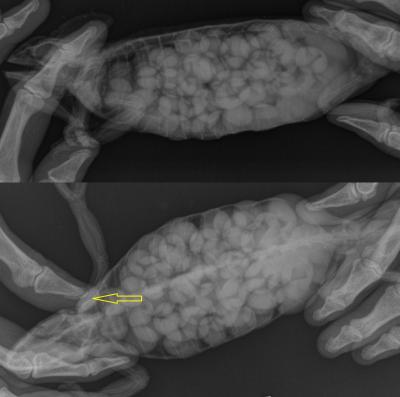

Náš předpoklad jsme potvrdili pomocí rentgenových snímků. Tenká slupička těla byla vyplněna vajíčky (vzájemně se překrývající bílé oválky). Dále byla zjištěna zlomenina kosti pažní (žlutá šipka), způsobena odvápněním kostry. Všechen vápník totiž dávala samička do tvořících se vajíček.